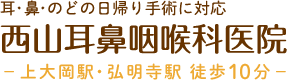

扁桃肥大とは

喉の奥にある扁桃(口蓋扁桃)が何らかの原因で肥大してしまう病気で、呼吸がしにくく、いびきや無呼吸症候群の原因にもなります。また、食事を飲み込むのに時間がかかります。治療には手術が必要な場合もあります。

喉の奥にある扁桃(口蓋扁桃)が何らかの原因で肥大してしまう病気で、呼吸がしにくく、いびきや無呼吸症候群の原因にもなります。また、食事を飲み込むのに時間がかかります。治療には手術が必要な場合もあります。